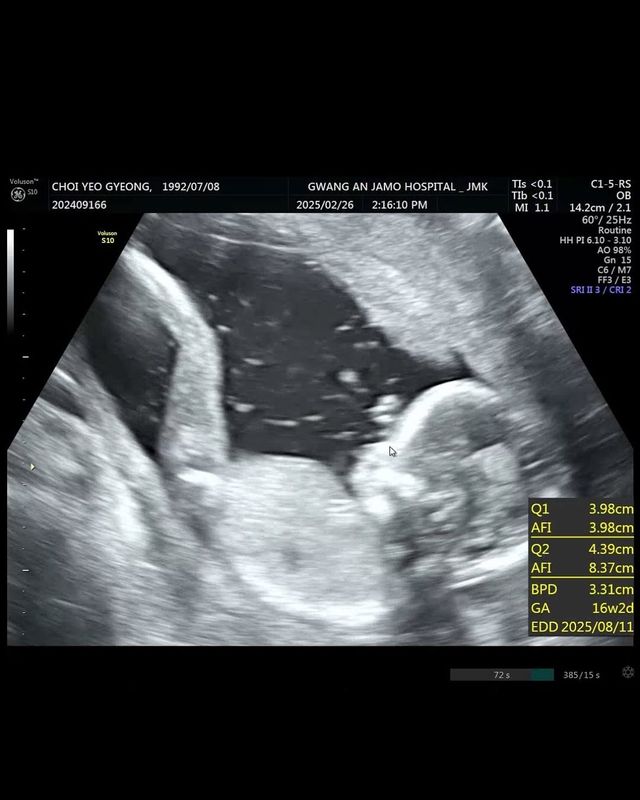

1일 현숙은 SNS에 "결혼 준비하며 정말 큰 축복이 찾아왔다. 둘이 아닌 셋으로 축복받는 오늘이었다"는 글과 함께 초음파 사진을 공개했다.

1일 두 살 연하 비연예인과 결혼식을 올린 현숙은 "꿈은 반드시 이루어진다. 우리 공주 다리 길죠? 벌써부터 딸바보 예약"이라고 하며 "이제 저도 예비맘이다. 정말 너무 행복하다"고 전했다.